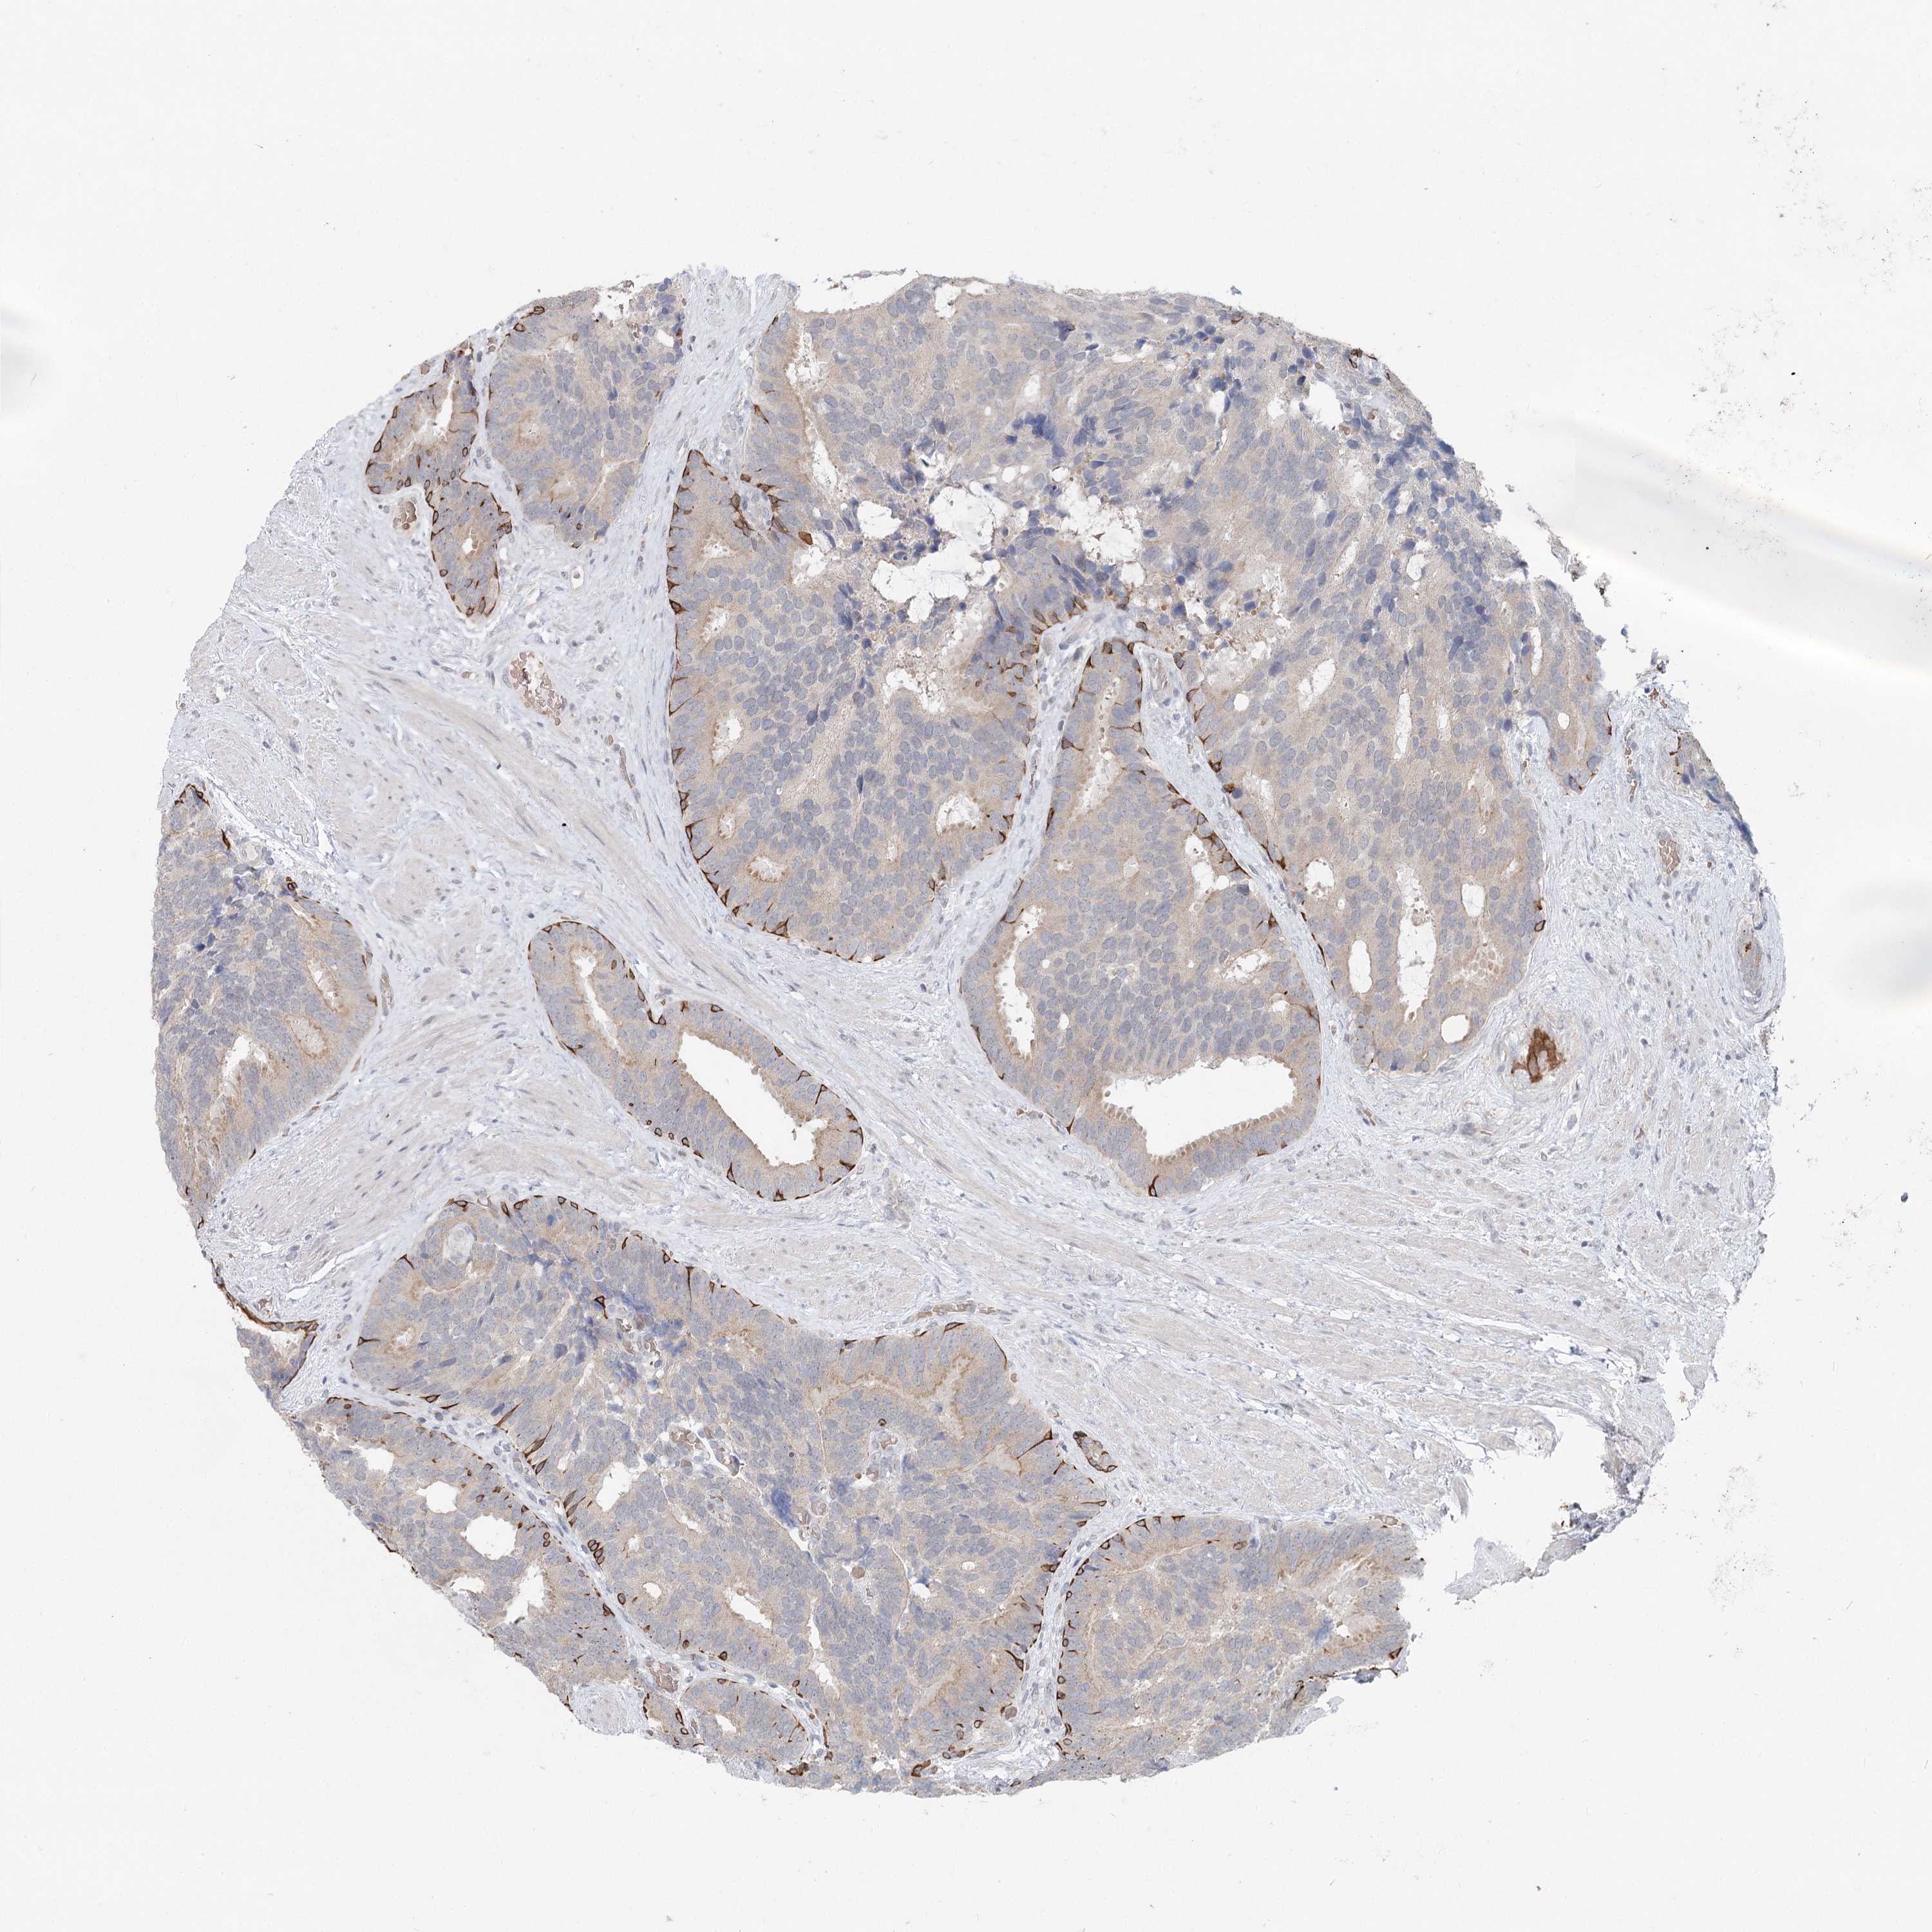

PROSTATE CANCER - Protein expressioni

A mouse-over function shows sample information and annotation data. Click on an image to view it in a full screen mode. Samples can be filtered based on level of antibody staining by selecting one or several of the following categories: high, medium, low and not detected. The assay and annotation is described here.

Note that samples used for immunohistochemistry by the Human Protein Atlas do not correspond to samples in the TCGA dataset.

Antibody stainingi

Antibody staining in the annotated cell types in the current human tissue is reported as not detected, low, medium, or high, based on conventional immunohistochemistry profiling in selected tissues. This score is based on the combination of the staining intensity and fraction of stained cells.

Each image is clickable and will lead to virtual microscopy that enables deeper exploration of all samples and also displays staining intensity scores, fraction scores and subcellular localization as well as patient and tissue information for each sample.

Antibody HPA032114

Antibody HPA057352

Antibody CAB034296

Staining

High

Medium

Low

Not detected

Intensity

Strong

Moderate

Weak

Negative

Quantity

>75%

75%-25%

<25%

None

Location

Nuclear

Cytoplasmic/membranous

Cytoplasmic/membranous,nuclear

Adenocarcinoma, NOS

Adenocarcinoma, High grade

Adenocarcinoma, Low grade